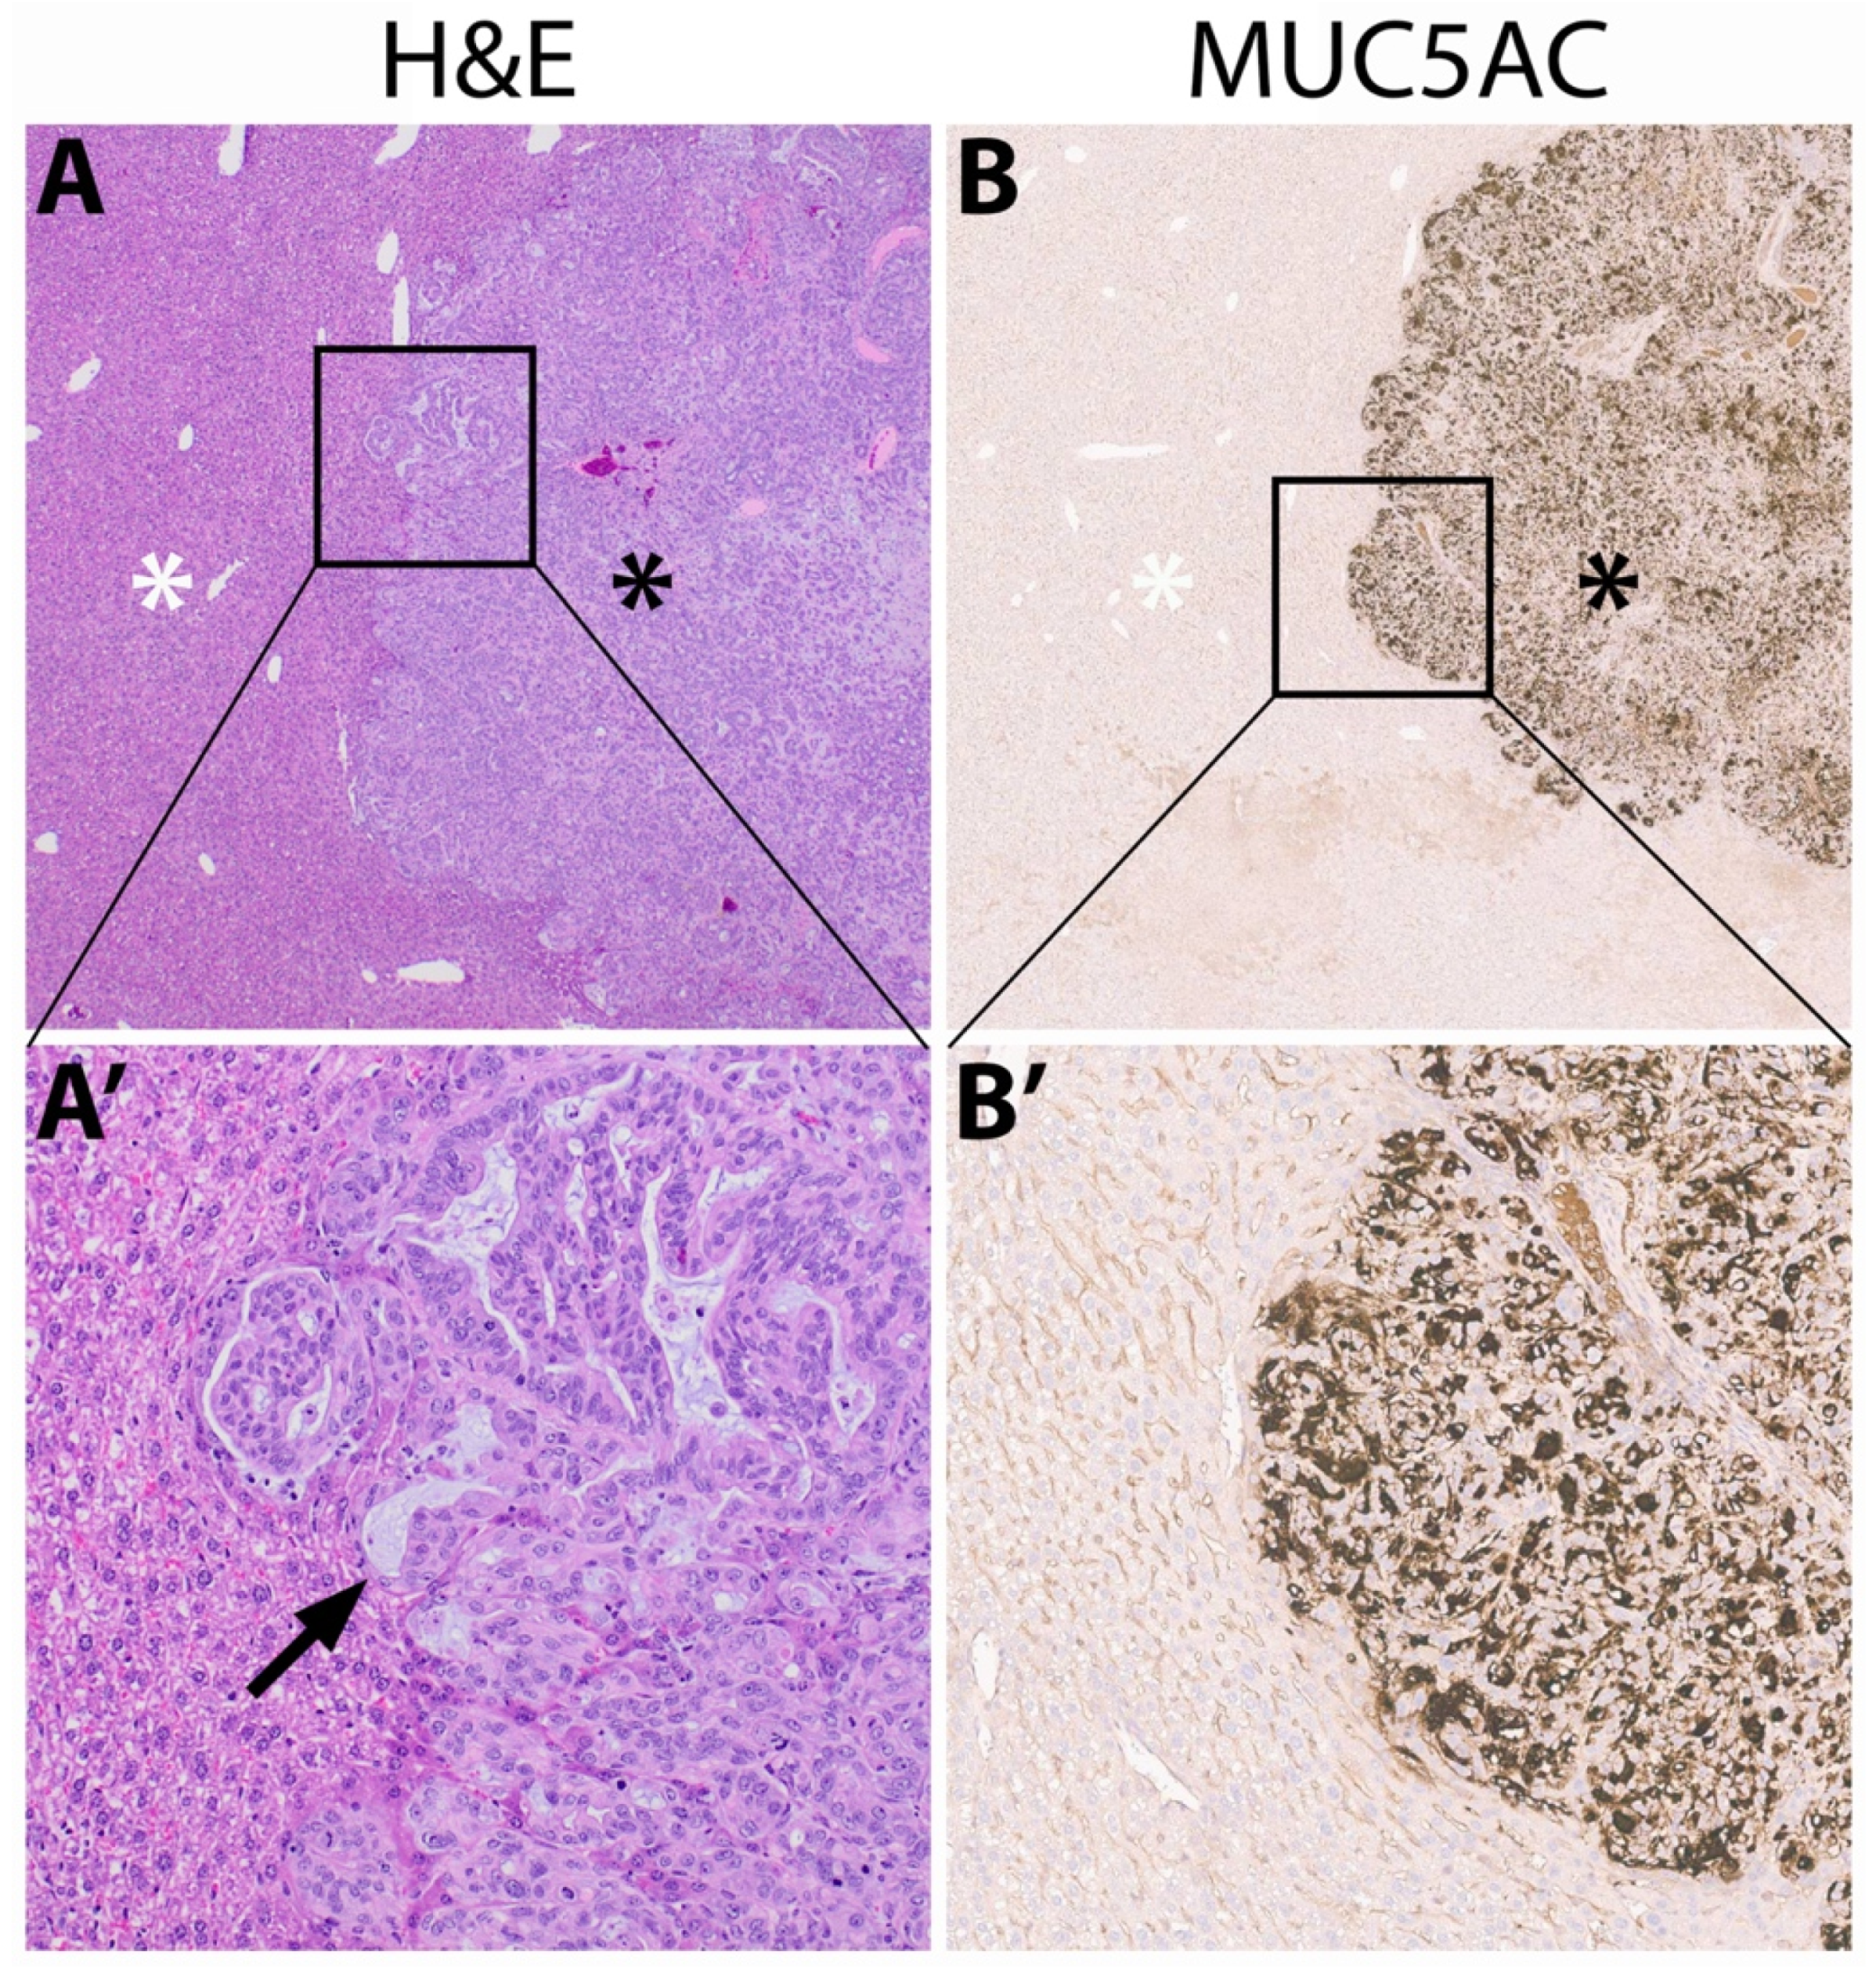

3.5. Immunohistochemistry of Mucin